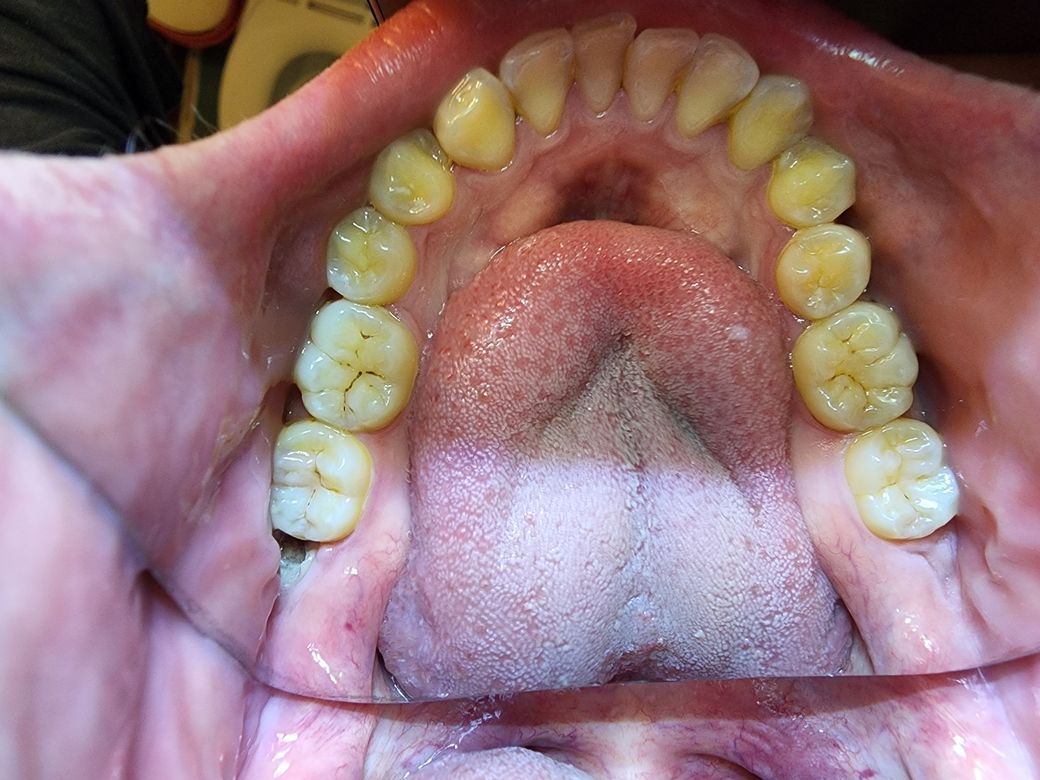

2015년 엑스레이 사진, 그리고 현재 2022년에 찍은 상악 1개 사진과 하악 2개 사진이에요.

- 하악에 사랑니

엑스레이로는 사랑니 둘 다 보여야하는데 막상 찍으니 사랑니 하나는 안 보이고 하나는 이미 썩어서 아주 그냥 치아에 호수가 형성되었네요..

그리고 전체적으로 입 안 깊이 갈수록 잘 안 보이는 치아일수록 상태가 안 좋은 것 같아요.

지금 당장 통증은 없는데 시간 문제일것 같기도 하고..모르겠어요.

사랑니는 충치가 심하여 발치가 필요해보입니다. 치과에서 검사를 받아보시기 바랍니다. 감사합니다.

사랑니만 발치하시길 바랍니다. 물론 유치 자체가 상태가 좋아 보이지 않아 치료를 할 수 있는 상태가 아닌 발치를 해야할 수 있어 보입니다. 하지만 현재 사진에서 사랑니는 빼셔야 할 것으로 보이며 계속해서 방치시 어금니까지 영향을 주어 어금니까지 손상시킬 수 있어 보입니다. 유치의 경우에는 통증이나 불편감이 없다면 쓸때까지 쓰고 치료하시는 것이 좋아 봉비니다.